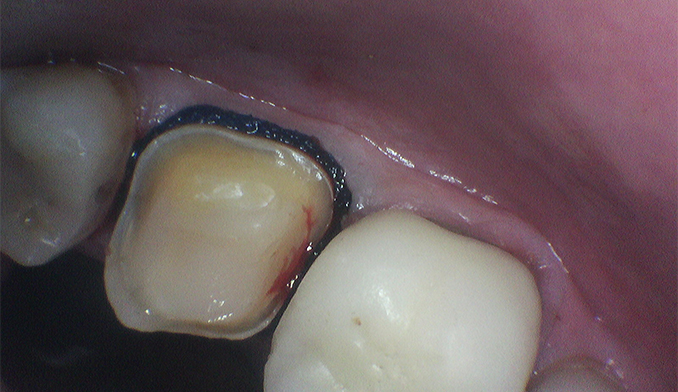

Gumline Bonding for Esthetics and Protection

The patient requested bonding along the gumline to improve appearance and protect exposed areas. We placed tooth-colored fillings to restore a smooth, natural look and enhance long-term oral health.